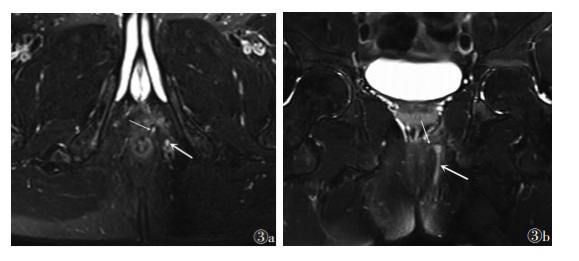

| 图 3 男,43岁,单纯经括约肌瘘管(Ⅲ级) 图 3a 轴位脂肪抑制T2WI显示瘘管内口(细箭)、瘘管位于外括约肌的外侧(粗箭) 图 3b 冠状位脂肪抑制T2WI显示瘘管经内外括约肌(细箭)走行于外括约肌的外侧(粗箭) |

![]() |